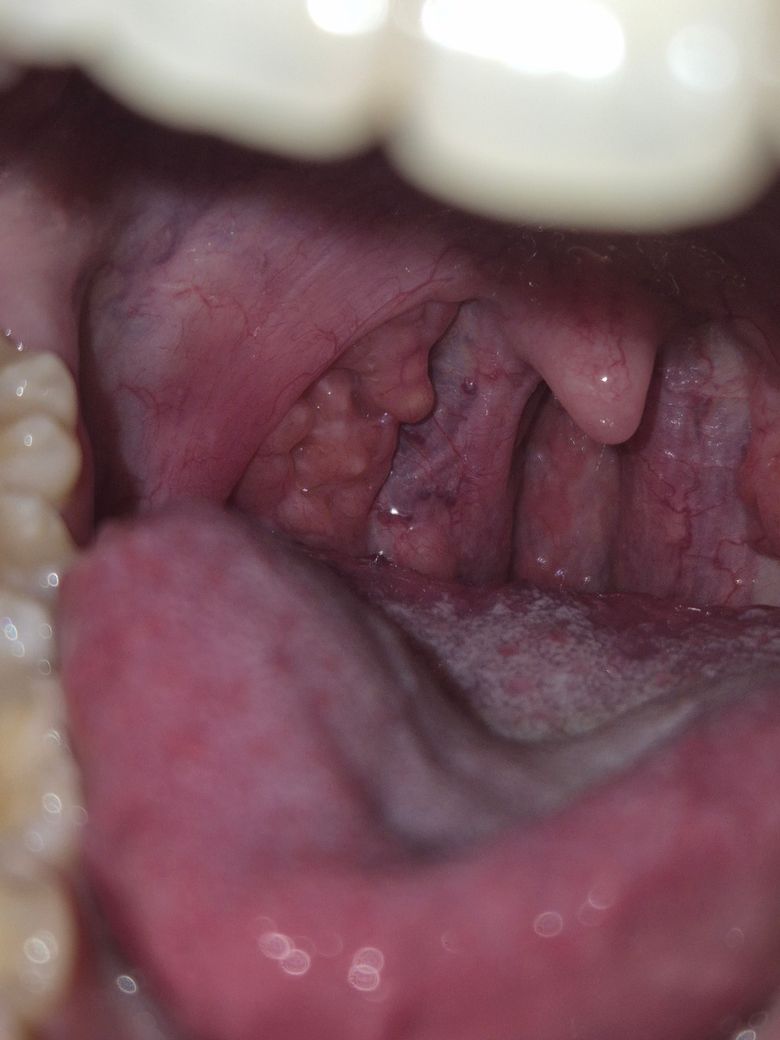

제 편도 모양 괜찮은건가요?????

만28세 여성, 비흡연자, 음주도 거의 안 하고 가다실 접종도 다 마쳤습니다.

어렸을 때 부터 편도결석이 생겨서 그런지 편도 모양이 좀 변한 거 같은데요,

얼마 전에 편도암 관련된 글을 보고 나니 걱정이 되서 질문합니다.

가끔 편도 통증이 일시적으로 있다가 금방 사라지는 증상이 있고 모양이 좀 이상한 거 같아서요.

제 편도 괜찮은건가요?

• 1번 째 사진

• 안녕하세요. 이송재 이비인후과 전문의입니다.

네 사진상으로 보았을 때 양쪽 편도가 대칭은 아니지만 악성으로 보이지 않습니다.